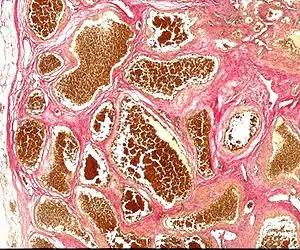

| Histology of a cavernous hemangioma | |

Cerebral cavernous malformation (CCM) is a cavernous hemangioma that arises in the central nervous system (CNS). It can be considered to be a variant of hemangioma, and is characterized by grossly large dilated blood vessels and large vascular channels, less well circumscribed, and more involved with deep structures, with a single layer of endothelium and an absence of neuronal tissue within the lesions. These thinly walled vessels resemble sinusoidal cavities filled with stagnant blood. Blood vessels in patients with cerebral cavernous malformations (CCM) can range from a few millimeters to several centimeters in diameter. Most lesions occur in the brain, but any organ may be involved.[1]